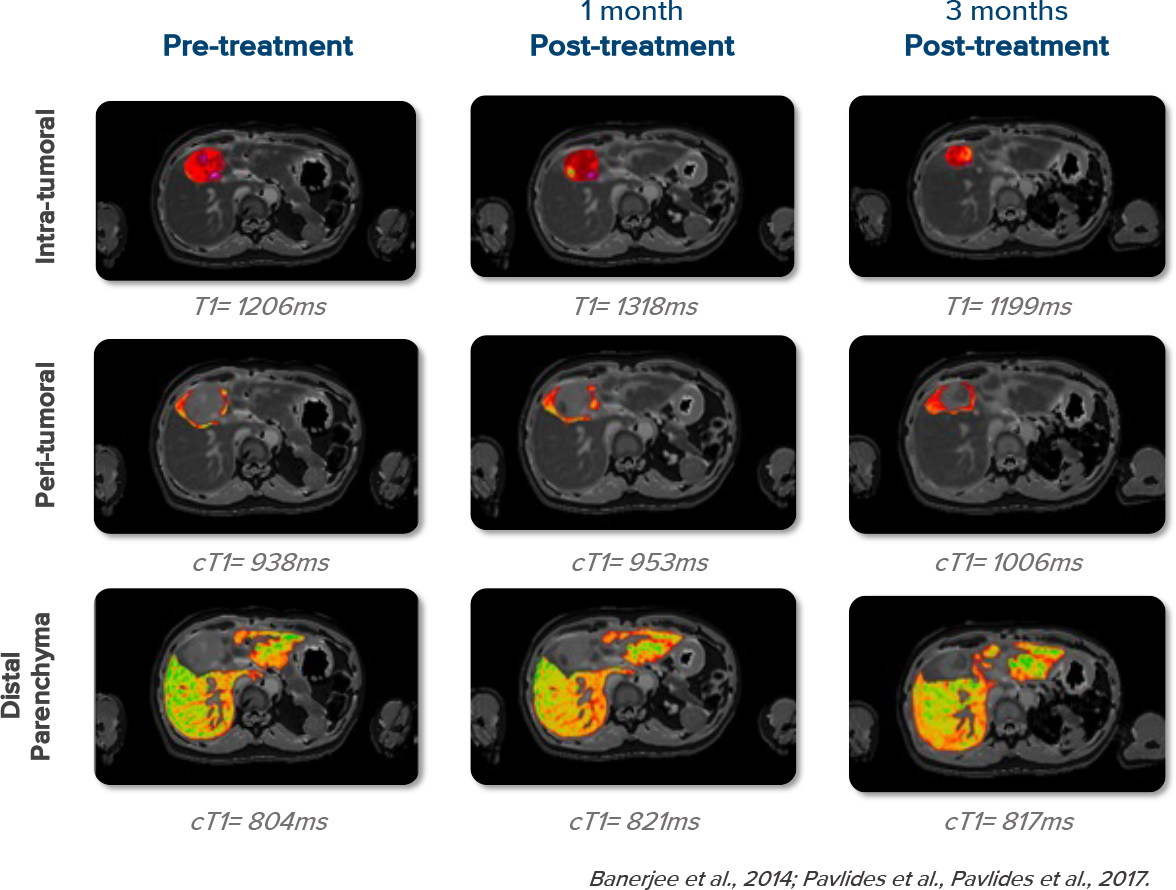

Enhanced screening and monitoring with cT1

cT1 better identifies patients for enrolment, more accurately detects early efficacy signals and pseudo-progression, and quantitatively monitors drug-induced liver injury.